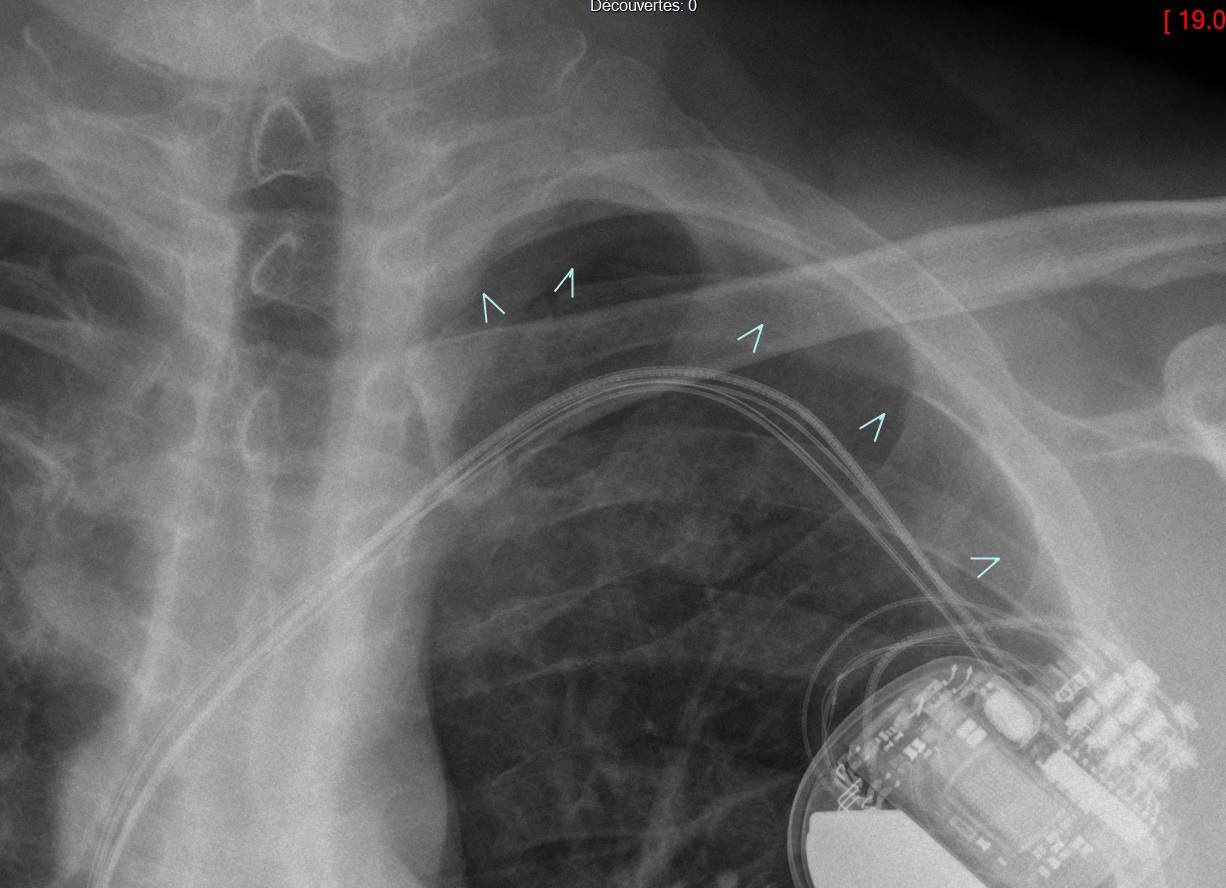

Defibrillateur

- Aspect épaissi = coils de défibrillation

Auricule droit + ventricule gauche + PM ventricule droit avec 2 coils de défibrillation le long du cable